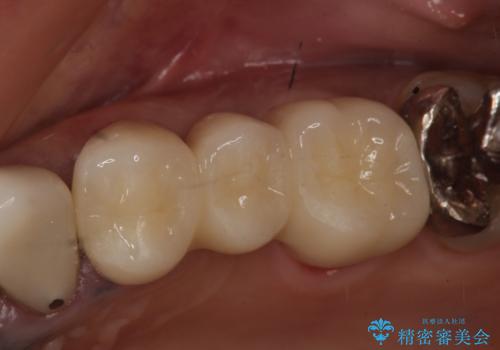

- 昔治療した左上56の延長ブリッジをきちんと治療しなおしたいといらっしゃった方の症例です。

古いブリッジを除去後、オールセラミッククラウンによる補綴を行いました。

- オールセラミッククラウン…¥100,000×3、仮歯…¥10,000×3費用は治療当時の料金となります